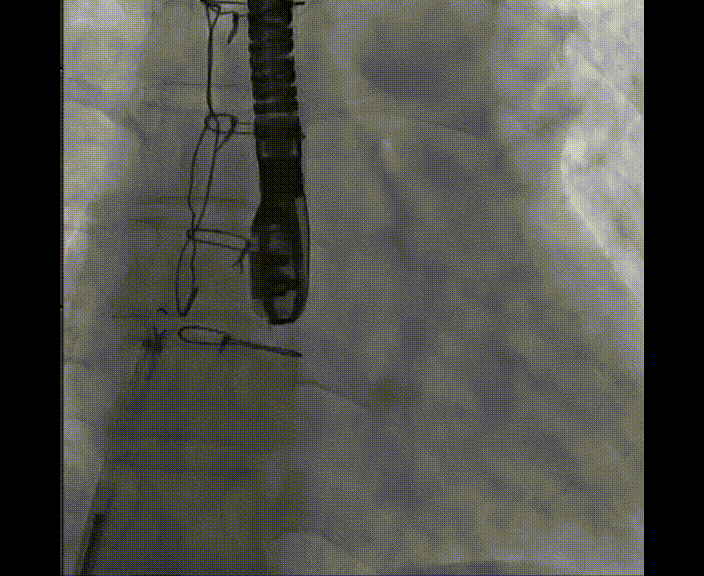

術(shù)中首先在局麻下穿刺股動脈、股靜脈,完成心導(dǎo)管檢查評估后轉(zhuǎn)為全麻,在食道超聲引導(dǎo)下穿刺房間隔,穿刺成功后將加硬導(dǎo)絲送入左上肺靜脈建立軌道,根據(jù)患者病情行球囊預(yù)擴(kuò)張后植入6mm孔徑房間隔造孔支架,經(jīng)透視及食道超聲評估支架左右盤展開良好,夾持于房間隔兩側(cè),固定穩(wěn)定、位置良好,食道彩超顯示房水平右向左為主分流,分流孔直徑符合預(yù)期大小,心導(dǎo)管檢查評估達(dá)到預(yù)期效果,釋放造孔支架。術(shù)后12h患者下床活動,恢復(fù)順利,擬于近日完善術(shù)后評估后出院。